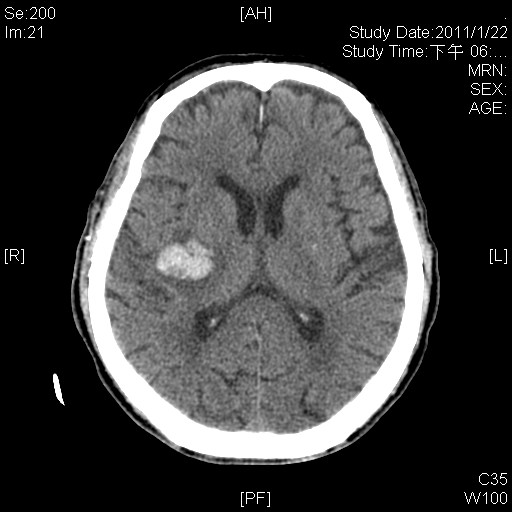

顱內出血--ICH, right basal ganglion

大腦右側基底核的出血性中風